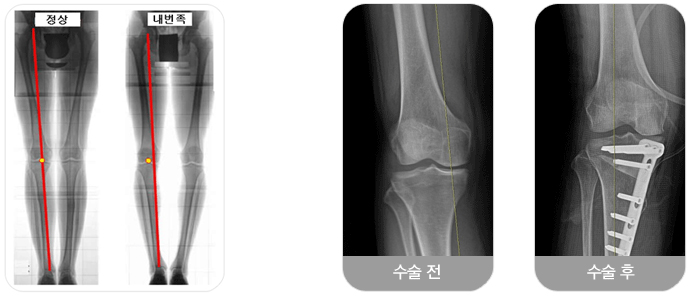

퇴행성 관절염은 대개 무릎의 내측 부위부터 시작되어 외측으로 진행되는데, 내측 부위에만 관절염이 발생한 60대 이하의 환자의 경우에는 근위 경골 절골술이 치료의 대안이 될 수 있습니다. 무릎 내측에 관절염이 발생하면 무릎은 내반(O자 다리)변형이 생깁니다.

정상 무릎은 체중이 무릎의 중앙을 통과해서 발목으로 전달이 되는데, 무릎이 내반되면 체중이 무릎의 내측으로 전달되어 이미 손상된 내측 부위로 과도한 체중이 부하되고 퇴행성 관절염이 급속히 악화된다.

HTO는 60대 이전에 무릎 안쪽에만 관절염이 발생해있고 내반 변형이 생긴 환자에서 시행합니다. 모든 환자에서 수술이 가능한 것은 아니고 무릎이 과도하게 내반된 경우, 무릎이 90도 이상 안 구부러지거나, 무릎이 15도 이상 안 펴지는 경우 과도한 비만 등의 경우는 수술이 불가능 합니다.

먼저 HTO 수술 전에 관절경을 시행해서 무릎 외측 부위에 있는 연골 상태의 정상 유무를 확인하고 정상인 경우에 HTO 수술을 진행한다.

수술 방법은 종아리뼈(경골) 상단에서 아랫쪽으로 약 5,6cm 되는 부위를 절골한 후 뼈를 벌려서 쐐기 모양의 빈 공간을 만들면 무릎의 내반 변형이 교정이 되는데, 이때 좀 더 과하게 교정을 해서 무릎의 바깥 부분으로 체중이 부하되도록 한다.

이 상태에서 금속판을 이용해서 교정된 뼈를 고정하고, 쐐기 모양의 빈 공간은 뼈 이식을 통해서 결손을 채운다. 이렇게 HTO 수술을 하면 수술 후에, 연골이 망가진 내측으로 체중이 전달되지 않고 외측에 있는 정상 연골로 체중이 전달되기 때문에 무릎의 통증이 감소된다.